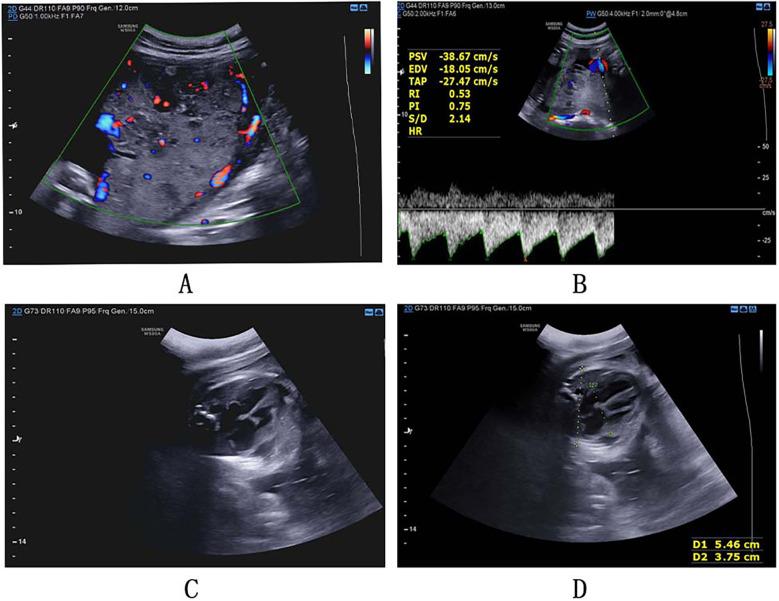

Placental chorioangiomatosis: a case report and literature review.

The placenta is a highly specialized temporary organ during pregnancy. As the hinge of material exchange between mother and fetus, it plays a crucial role in maintaining the fetus's intrauterine life and growth period of fetus. Placental lesions or dysfunction can cause pregnancy diseases. Placental chorioangioma is a benign tumor originating from the placental with an incidence rate of 1%, whose etiology has not yet been fully elucidated. Prenatal diagnosis can usually be done by clinical ultrasound. However, placental chorioangiomatosis, as a placental choriovascular disease, is rarely reported or studied at home and abroad. Due to the unclear etiology and pathogenesis, prenatal diagnosis of placental chorioangiomatosis before early recognition of severe maternal and fetal complications during pregnancy is sparse. Therefore, patients cannot be effectively treated, and pregnancy outcomes are often poor. Herein we provide a case at our hospital and conduct a series of literature reviews around this case to further improve the understanding of placental chorioangiomatosis, and promote early recognition and early intervention.